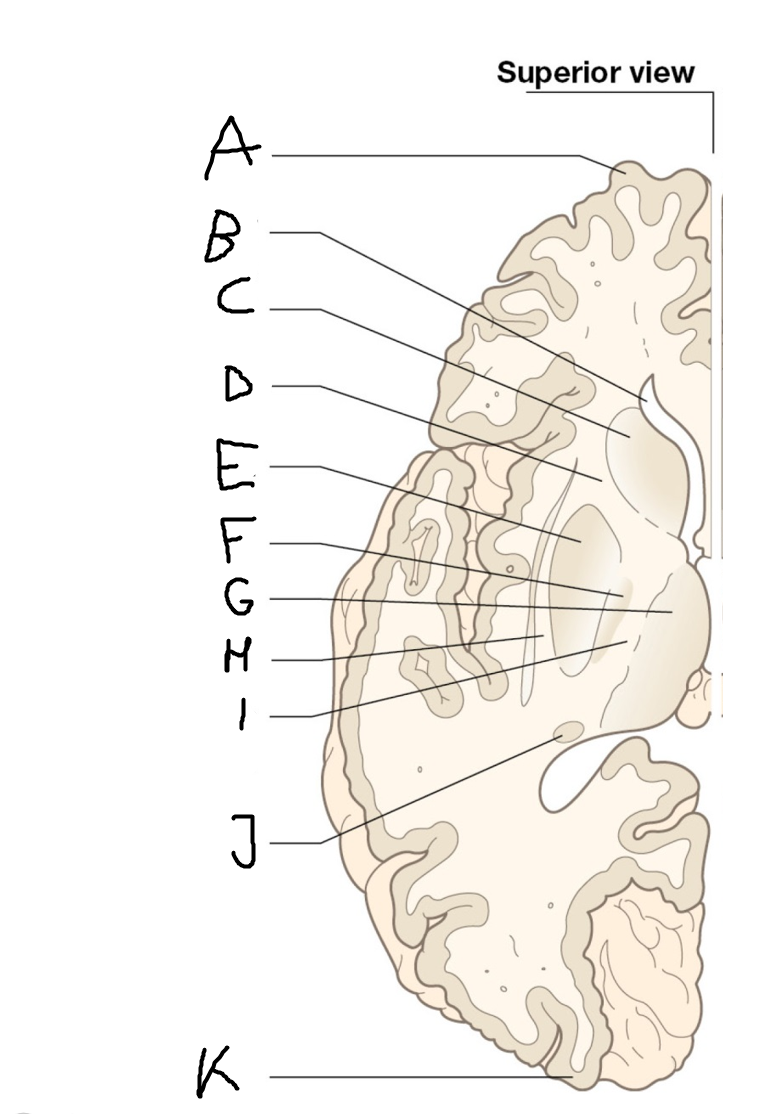

internal capsule (posterior limb)

B

anterior horn of lateral ventricle

C

head of caudate nucleus

D

internal capsule (anterior limb)

E

putamen

F

globus pallidus

G

Thalamus

H

External capsule

I

internal capsule (posterior limb)

J

tail of caudate nucleus